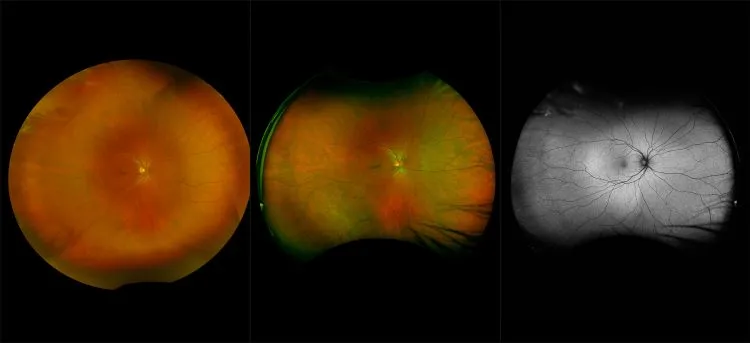

optomap® Recognizing Pathology

This material is designed as a searchable reference resource to support clinical decision-making. The information contained here should be used as general guidance when viewing optomap and OCT images from Optos devices. The differential diagnosis should be made under the direction of the responsible physician. These images were taken on the latest ultra-widefield optomap devices.

The Cases and Images

optomap Recognizing Pathology is searchable by pathology and/or optomap image modality. You may search by multiples of each selection. Each individual case is represented by the accompanying thumbnail image. Most cases include several different optomap image modalities. To view a full description of the case, please click on the thumbnail. Each image in the case will be made available through our OptosAdvance software which provides multi-dimensional visualization of digital images to aid in the analysis of anatomy and pathology. Support and pathology definitions can be found by selecting one of the buttons, above. Should you have questions, please complete the form below.